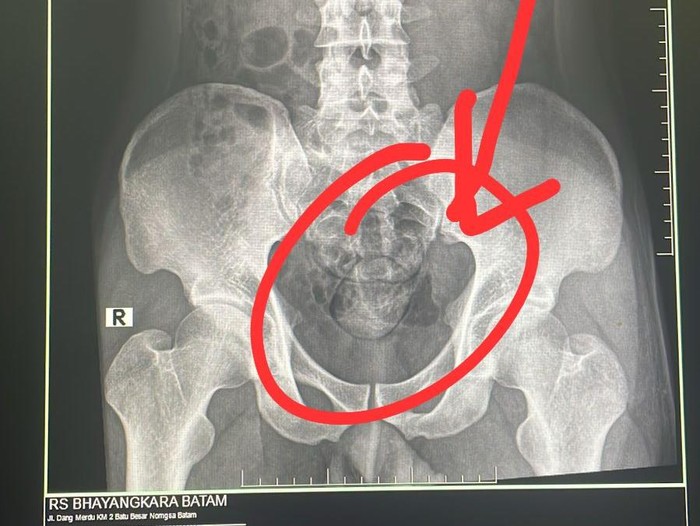

Penampakan hasil rontgen ditemukan dua buah kapsul berisi narkoba di dalam anus milik AB (24). (Foto: Polda Kepri)

Selanjutnya, pelaku dibawa ke RS Bhayangkara Batam untuk menjalani pemeriksaan rontgen di bagian radiologi. Dari hasil pemindaian, ditemukan dua kapsul plastik di dalam tubuh pelaku.

“Setelah hasil rontgen keluar, pelaku mengeluarkan dua kapsul tersebut di toilet RS Bhayangkara. Total berat sabu mencapai 100 gram,” katanya.